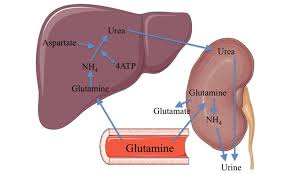

قیمت: 35٬000 تومان - دسته بندی فایل: پاورپوینتپاورپوینت متابولیسم اوره در انسان و دام (ppt) 22 اسلاید

فروش ویژه پاورپوینت حرفه ای متابولیسم اوره در انسان و دام / تعداد اسلاید: 22 اسلاید